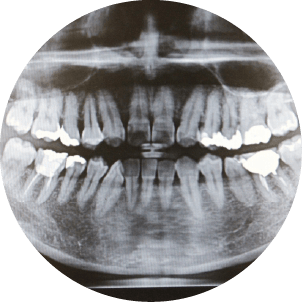

カウンセリング後、口腔内の状態を詳しくチェックするため、レントゲンや口腔内写真を撮影します。虫歯や歯周病がある場合には、その治療が優先されます。

検査により、患者さまの歯や歯周組織の健康状態を確認し、最適な治療方法を選択するための基礎情報を得ます。